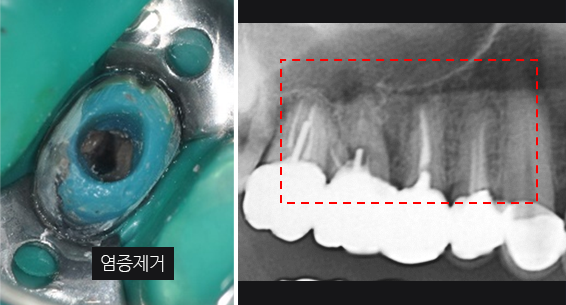

잇몸 염증으로 내원, 기존 보철물 수복시 신경관을 제대로 치료하지 못하여 염증이 재발된 상황이었습니다. 고운미소에서는 기존 포스트를 제거하고 오염된 부위에 약재를 삽입하여 염증을 제거하는 신경치료를 시행하였습니다.

기존 포스트 제거

근관내 약재 삽입

치근단 부위 회복

염증을 제거하는 신경치료 후 치근단 부위가 빠르게 회복되어 깔끔하게 신경치료를 완료하고 크라운 보철물을 씌웠습니다. 신경치료를 받은 치아는 약해져 있기 때문에 크라운 보철물로 씌워주어 세균 감염을 예방해야 합니다.